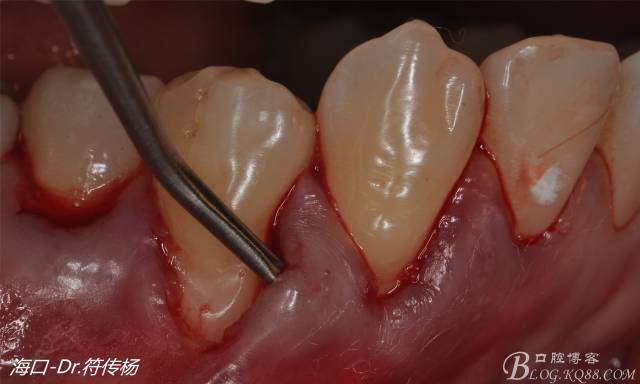

然后使用下頜開隧刀剝離牙齦

最后使用牙齦乳頭分離器分離牙齦乳頭